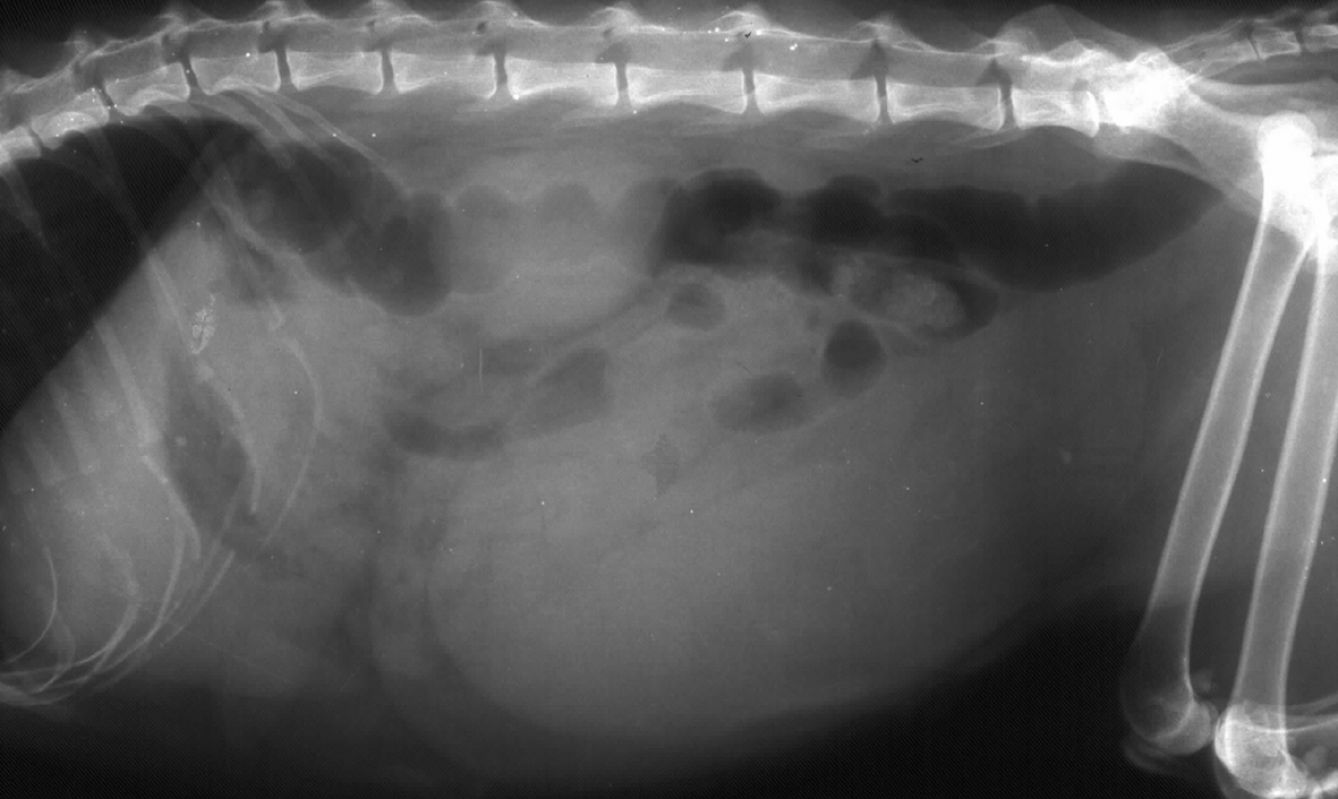

Les chiennes incluses devaient bien sûr présenter un pyomètre non compliqué, mais aussi être exemptes de diabète, d'hyperadrénocorticisme, ou d'immunodépression, et peser 3 kg au moins. Pour exclure la présence de choc septique, les chiennes présentant une température > 39,4° C et soit une leucopénie (< 5,05 109/l) soit une hypoglycémie (< 4,28 mmol/l) ou les deux ont aussi été exclues. L'intégrité de l'utérus était vérifiée pendant l'intervention et si une effraction était observée, l'animal était également exclu. Un consentement éclairé quant à l'étude était recueilli auprès des maîtres avant l'intervention et un traitement péri-opératoire (prophylactique) à base sulfamides potentialisés était administré à l'animal (par voie IV avant l'incision). Entre juin 2019 et octobre 2023, 153 chiennes ont été incluses dans l'essai.